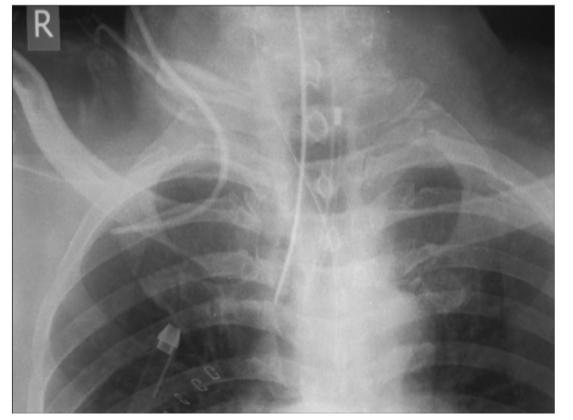

Prior to using the central line